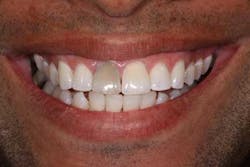

Of all the problems that can occur with implant placement in the anterior, not controlling the zenith of gingival contour may be the most troublesome when it comes to anterior esthetics. Gingival zenith or height of gingival contour is defined as the apex of the gingival height. There are many ways to lose several millimeters of peri-implant mucosa, and it has been shown that even a 1 mm apical displacement of peri-implant mucosa may result in insurmountable limitations in anterior implant esthetics. Things such as deep implant placement, buccal resorption, and relative tooth eruption are just some of the things that can cause this loss of tissue.

Now comes the tricky part — the provisional. Prosthetic control of peri-implant tissue is achieved by properly utilizing your abutment and provisional form. When placing the provisional, it is important to maintain gingival zenith. When fabricating a provisional, my rule of thumb is to create a flat or slightly convex surface facially and lingually, and a concave surface interproximally. This will minimize impingement on the tissue interproximally and, if anything, allow for “overgrown tissue” to develop. This tissue can be easily contoured prior to final placement to give an ideal esthetic gingival architecture.

Usain Bolt trained for years to prepare for a 10-second Olympic race, a race that made him a world superstar. He didn’t walk up to the track the day of the Olympics and blow away the competition. He spent countless hours preparing physically and mentally for that one moment in the spotlight. The same dedication applies to dentistry. When an anterior implant case is planned properly among the surgeon, dentist, and ceramist, the result can be as rewarding as Olympic gold.Before

Before